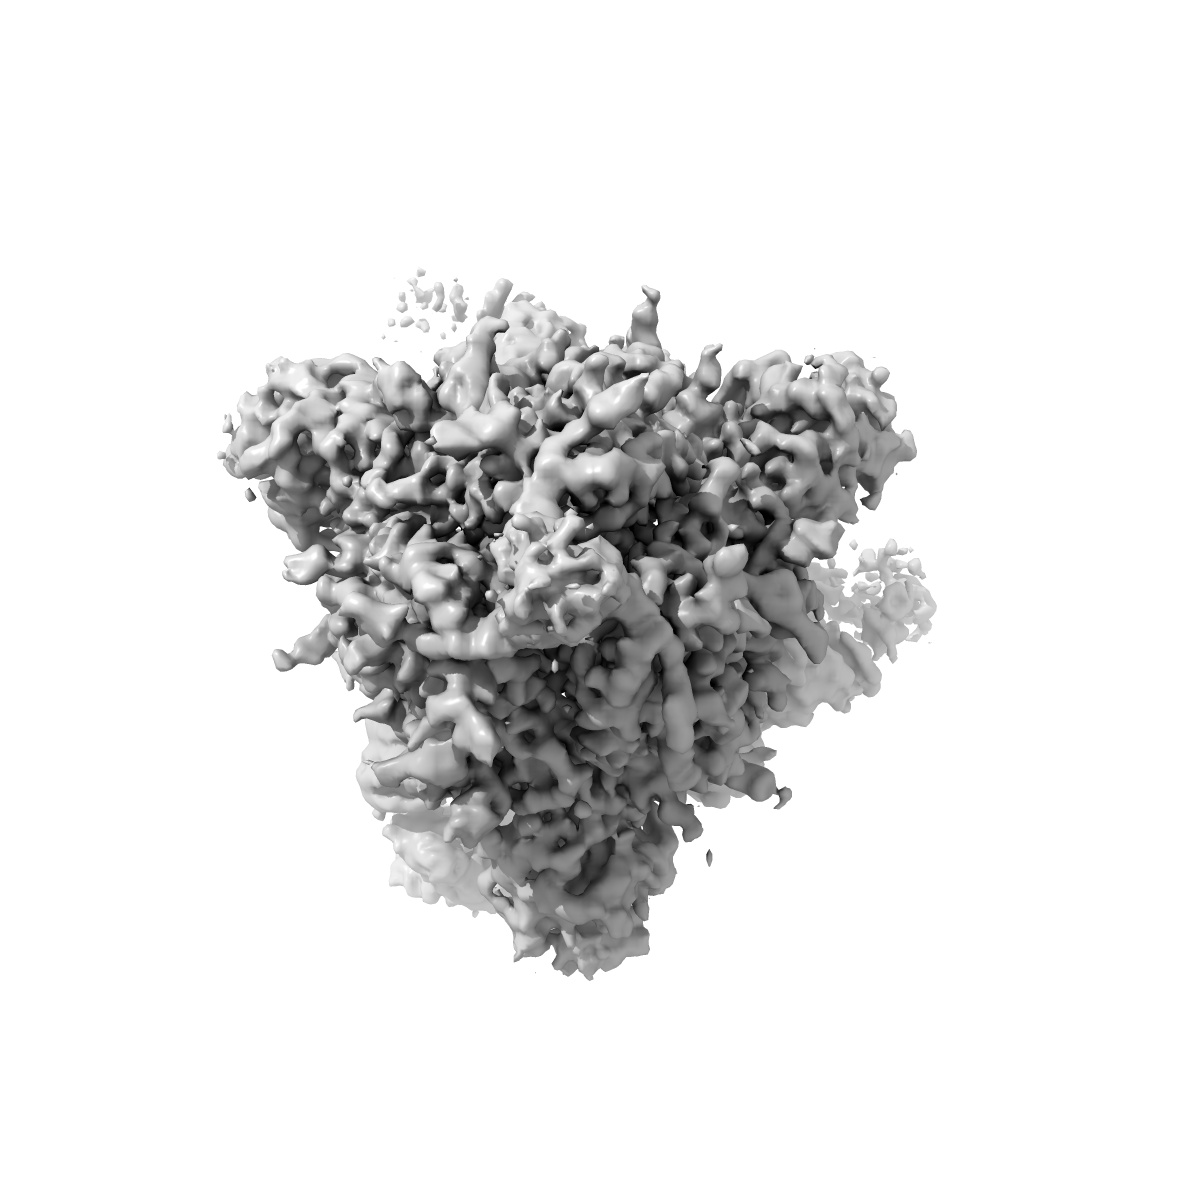

CryoEM map of SARS-CoV-2 S protein in complex with Receptor Binding Domain antibody DH1047

Single-particle3.4 Å

Sample: Severe acute respiratory syndrome-related coronavirus spike glycoprotein in complex with RBD antibody DH1047

Fitted models: 7ld1